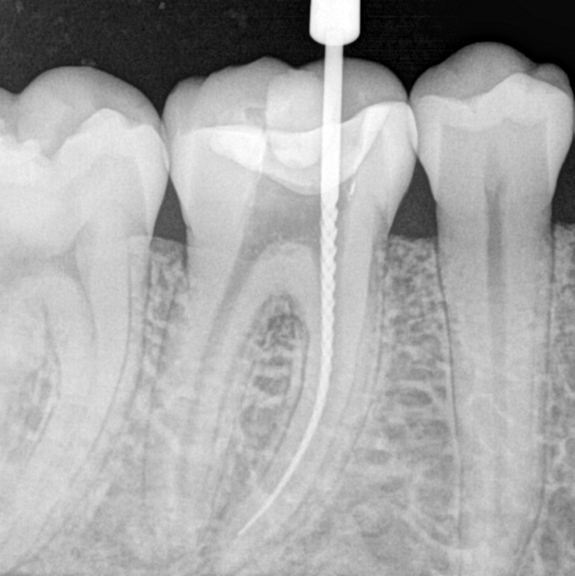

Kanal tedavisi lokal anestezi altında yapılır ve ağrı duyulmaz. Dişin ağızda görünen kuron kısmından dişin sinir tabakasına açılan bir oyuktan dişin çene kemiği içindeki kök kısmına giriş yapılır. Dişler 1, 2, 3 kanallı olabilir; hatta bazı dişlerde normalden fazla sayıda kanal bulunur. Kanal tedavisi işlemi; sinirlerin alınması, kanalların şekillendirilip mikroorganizmalardan arındırılması ve daha sonrasında genişletilmiş kanalların doldurulması işlemidir. Daha sonra dişin kuron kısmına harabiyetin büyüklüğüne göre restorasyon yapılır ve dişin estetik ve fonksiyonel devamlılığı sağlanır.

Kliniğimizde klasik radyografilerin yanında dijital radyografiler de tedavinin her aşamasında kullanılmaktadır.